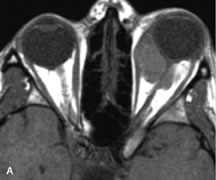

PATIENT PREPARATION Before MRI is performed, patients must be screened and prepared to avoid the potential hazards associated with the strong magnetic field. Patients who have ferrous aneurysm clips or cardiac pacemakers, who depend on life-support equipment, or who retain a possible metallic intraocular foreign body are not candidates for this imaging modality. MRI cannot be performed on obese patients who cannot fit into the bore of the magnet. Patients who are claustrophobic may not tolerate a prolonged period of study within the confines of the magnet, whereas others might do well if given a mild sedative. All worn metallic objects (e.g., necklaces, watches) should be taken off, credit cards set aside, and eye makeup removed before entering the room containing the magnet.5,20,34,35,36 NORMAL ORBITAL ANATOMY T1-weighted images provide the best anatomic details of the orbit because they display superior contrast resolution between normal structures (see Fig. 8). The vitreous has a long T1, resulting in an intermediate signal similar to brain, whereas the crystalline lens and sclera appear dark because of a longer T1 and short T2. The extraocular muscles, like all skeletal muscles, demonstrate a moderately long T1 and short T2 and highly contrast with the intense signal of the surrounding orbital fat (adipose tissue has an extremely short T1). The lacrimal glands appear as mottled areas of reduced intensity of the signal from the orbital fat in the lacrimal fossa. The optic nerves are seen with the same signal intensity as brain white matter and are hypointense relative to the orbital fat because their Tl is longer than the Tl of fat but shorter than the Tl of water. Cortical bone is not well delineated because it contains little free water, yielding minimal signal in MRI, and thus appears dark on all pulse sequences. This feature explains why MR images of the orbital apex and intracanalicular portion of the optic nerves are superior to comparable CT scans. Partial volume averaging of the bones in these regions obscures soft tissue details on CT images, whereas MRI reveals the signals only from the soft tissue structures with no cortical bone input. Bone marrow, on the other hand, is seen as a relatively intense signal because of its high fat content (see Fig. 8).37,38 T2-weighted pulse sequences are not ideal for imaging normal anatomy; however, they are particularly useful in revealing pathologic conditions (see Fig. 9). T2-weighted studies are most easily recognized by a bright vitreous signal. ORBITAL DISEASES Vascular Lesions Cavernous hemangiomas appear as well-circumscribed, smooth, usually intraconal masses that are isointense to muscle on T1-weighted images and hyperintense on T2-weighted images (Fig. 12). Patchy early enhancement is typically followed by diffuse, more homogeneous enhancement.39 The internal architecture of the mass, including septation and internal vasculature, may often be appreciated with high-quality orbital imaging.40 Lymphangiomas consist of ectatic vascular channels within a connective tissue stoma with varying degrees of lymphoid cellularity. On MRI, these tumors are typically poorly circumscribed, multicompartmental, and heterogeneous, often showing cystic dilations with fluid levels (Fig. 13). The signal characteristics within lymphangiomas vary considerably, reflecting cystic and solid components and the varying paramagnetic characteristics of blood at different stages of degradation.40–42 Acute hemorrhage appears hypointense on both T1- and T2-weighted formats. Methemoglobin present in subacute hemorrhage (3 to 14 days) leads to hyperintense signal on both T1- and T2-weighted images.41 A small percentage of lymphangiomas appear radiologically indistinct from orbital cavernous hemangiomas.43 Orbital varices are venous malformations that expand with increased systemic venous pressure, such as with Valsalva maneuvers. Because rapid acquisition of images during a Valsalva maneuver is important in imaging such a lesion, conventional or spiral CT is currently the modality of choice.44 MRI is an excellent modality for demonstrating enlargement of the cavernous sinus and dilation of the superior ophthalmic vein in patients with high-flow carotid-cavernous fistulas (Fig. 14).37MRA may be helpful in the evaluation of the venous outflow pattern. The rapidly flowing blood in these vascular structures carries the excited protons out of the section before they can be imaged, resulting in their dark appearance.5 In low-flow dural arteriovenous malformations, MRA may help define the arterial feeding vessels.45 Neural Lesions MRI is more effective than CT in delineating the intracranial optic nerves, chiasm, and optic tracts and, for this reason, is the preferred imaging modality in the evaluation of optic nerve disorders. The spatial relationships and image contrast of the orbital tissues with intraorbital optic nerve tumors is comparable between the two imaging modalities. The normal nerve is isointense to brain and appears enlarged and kinked owing to infiltration of an optic nerve glioma on T1-weighted images. Gliomas appear hyperintense on T2-weighted images and may be heterogeneous owing to cystic areas within the tumor. Contrast enhancement is variable.46 Intraorbital and intracranial optic nerve sheath meningiomas are usually isointense to cortical gray matter on Tl-weighted images and remain isointense on proton density studies (Fig. 15). Gd-DTPA is useful in delineating the intracranial extension of optic nerve meningiomas.7,47 The hyperostosis of bone and calcification associated with meningiomas are not demonstrated as well on MRI studies as on CT scans.20,37 Gd-DTPA–enhanced MRI also appears promising in the study of the permeability of the blood–brain barrier in selected optic neuropathies.22,48 MRI may reveal an enlarged optic nerve and some degree of contrast enhancement in cases of optic neuritis.49 Muscle Disorders Extraocular muscle enlargement in patients with thyroid-associated orbitopathy is demonstrated equally well with CT and MRI studies. However, the superior tissue contrast on MR images reveals better details of the relationships of the optic nerve to the thickened muscles at the orbital apex (Fig. 16).50 In addition, MRI may be able to differentiate between muscles that are enlarged as a result of edema and active inflammation and those enlarged because of fibrosis by their T2 relaxation times.21 Quantitative MRI was not found to be accurate in predicting the success of low-dose orbital irradiation.51 However, a muscular index relating the diameters of the rectus muscles to the bony orbital dimensions was useful in predicting optic nerve compression.52 MRI is also effective in imaging orbital tumors of mesenchymal origin, such as rhabdomyosarcoma, particularly in the assessment of extension into the anterior and middle cranial fossae (Fig. 17).37 The lack of any pathognomonic radiologic features necessitates rapid orbital biopsy when rhabdomyosarcoma is suspected. Osseous Lesions In general, CT is the imaging modality of choice when details of quantity and quality of bone are needed; however, abnormalities of bones can be detected indirectly by MRI. Cortical bone appears black (signal void) on MR images because of its low proton density and free-water content. The absence or discontinuity of the signal void of the orbital walls may represent bony destruction or fracture. Hyperostosis associated with prostate metastases or meningioma is visualized as areas of black smudging.50,53 Diseases in which the bone is replaced by pathologic tissues with a high free-water content, such as fibrous dysplasia, are well demonstrated on MRI. An intermediate signal intensity on T1-weighted images and hypointense signal on T2-weighted images is representative of fibrous dysplasia. Enhancement on post–Gd-DTPA MR scans is seen and is more evident in areas that are less mineralized.54 Cystic Lesions Dermoid cysts appear as rounded, well-defined lesions typically contiguous with an orbital bony suture. The high-intensity signal on T1-weighted images is attributed to the sebaceous-produced lipid contents (Fig. 18).31,50 Mucoceles may demonstrate a hypointense or hyperintense signal on MR images, depending on the concentration of proteinaceous or inflammatory fluid components. The integrity of the bony walls of the expanded sinus cavities cannot be assessed on MR as well as by CT.37,50,55,56 A high-signal intensity on Tl- and T2-weighted images is characteristic of orbital chronic hematic cysts because of the blood-breakdown products within the cysts.57 Trauma Although soft tissue relationships are usually better demonstrated on MRI, the evaluation of craniofacial bony trauma is preferable with CT. For example, prolapse of orbital fat through a fracture site and hemorrhage of adjacent tissues are demonstrated in an MR image, but the actual fractured bone is not imaged. Three-dimensional MRI of the orbit in subacute trauma has been described,58 although its precise role is not currently established. MRI has been suggested to be superior to CT in detecting intraorbital wooden foreign bodies.59,60 In a series of penetrating orbital injuries with organic foreign bodies, however, MRI was able to identify the foreign body in only four of seven cases.61 With an in vitro model for wood foreign body, McGuckin and colleagues concluded that CT was the imaging modality of choice.62 A careful history and, in selected cases, plain films to rule out a metallic foreign body are crucial before MRI is considered in patients with periocular trauma. MRI is particularly helpful in the detection and characterization of subperiosteal hematomas of the orbit (Fig. 19). They are most commonly seen in the subperiosteal space of the superior orbit as well-defined masses following a traumatic injury. The signal intensity varies depending on the acute, subacute, or chronic nature of the hematoma, based on the stage of blood degradation. Fresh hemorrhages are hypointense on T1-weighted images and hyperintense on T2 images. Hematomas that are 1 to 7 days old are hypointense on both T1- and T2-weighted images. T1-weighted images of hematomas more than a week old are hyperintense due to the oxidation of deoxyhemoglobin to methemoglobin, whereas the T2 images remain hypointense.63 Metastatic Tumors Breast carcinoma metastatic to the orbit has been demonstrated to be hypointense to the surrounding orbital fat on T1-weighted studies and hyperintense on T2-weighted images and has an affinity to the extraocular muscles (Fig. 20).50,64 The MRI characteristics of prostate carcinoma metastatic to the orbit have been described as involving the greater and lesser wing of the sphenoid, orbital roof, and optic canal. Diffuse bone hypertrophy with isointense or slightly hyperintense tissue on T1-weighted images represents the osteoblastic carcinomatous bone infiltration. Contrast enhancement is variable on T1-weighted and fat-suppressed images.65 Most other metastatic tumors also have a lower intensity signal on T1-weighted images and appear to displace or infiltrate normal orbital structures; however, their signal characteristics are variable on T2-weighted MR images.66 Many metastatic tumors demonstrate bright contrast enhancement with Gd-DTPA. Infectious Disorders MRI findings of preseptal and orbital cellulitis typically include increased signal intensities on T2-weighted images of the eyelids and orbital fat, respectively, due to the increased water content of the tissues. Since most cases of bacterial orbital cellulitis are associated with paranasal sinusitis, hyperintense signals of the affected sinuses may also be found on T2-weighted images as well as enhancement of polyps and granulation tissue on postgadolinium T1-weighted MR images. Subperiosteal abscess formation may occur due to contiguous spread of infection from the paranasal sinuses and appear on MRI as an area of intermediate signal on T1-weighted and proton-weighted MR images. The abscess may appear slightly hyperintense compared with muscle on T2-weighted scans with the necrotic contents having the greatest intensity.67 MRI and MRV are more sensitive than CT in revealing cavernous sinus thrombosis. Engorgement of the cavernous sinus, extraocular muscles, and ophthalmic veins is seen with hyperintensity of the thrombosed sinuses evident on all pulse sequences. The enlarged, thrombosed superior ophthalmic vein appears less hypointense than the normal contralateral ophthalmic vein, and hyperintensity within the lumen of the vessel may be seen on T1- and T2-weighted MR images.68 Inflammatory and Lymphoproliferative Lesions Inflammatory conditions of the orbit, both idiopathic (inflammatory pseudotumor) and those of known causes, have been found to be hypointense to fat and isointense to muscle on Tl-weighted studies and isointense or slightly hyperintense to fat on T2-weighted images (Fig. 21).50,64,69 The more fibrous or sclerosing varieties have less signal intensity on T2-weighted images. Marked enhancement is seen in pseudotumor infiltrates after gadolinium administration.70 The same signal characteristics are demonstrated in patients with Tolosa-Hunt syndrome, with mass lesions seen in the cavernous sinuses and orbital apices.71 Lymphomas have MRI characteristics similar to those of inflammatory lesions in that they are hypointense to fat and isointense to muscle on T1-weighted images (Fig. 22). They may appear hyperintense to fat on T2-weighted images, perhaps owing to less fibrosis than that seen in orbital inflammatory pseudotumor, although this is not a consistent finding.31,50,66 Lymphoid tumors typically enhance moderately after contrast injection. Unfortunately, studies have shown that tumor density and homogeneity are similar between inflammatory and malignant orbital infiltrates, and MRI cannot differentiate these lesions.72,73 Lacrimal Gland Tumors Lacrimal gland lesions present special problems in diagnosis and management. Pleomorphic adenoma (benign mixed tumor) should not be biopsied, but rather excised in toto. On the other hand, for lymphoma and inflammatory infiltrates, incisional biopsy is more appropriate than complete excision of the lacrimal gland. Thus, preoperative clinical and radiologic evaluation are especially crucial in planning appropriate surgical management. Pleomorphic adenomas demonstrate long T1 and T2 signal characteristics. They may show heterogeneity on T2-weighted images74 and moderate to marked enhancement with contrast.75 Signal characteristics of adenoid cystic carcinoma include hypointensity to fat on T1-weighted images, hyperintensity to fat with increased T2 weighting, and isointensity to fat on proton density-weighted studies (Fig. 23).31,75 Secondary bony alterations of the lacrimal fossa associated with lacrimal gland tumors, such as remodeling (benign mixed tumor) or destruction (adenoid cystic carcinoma), are seen indirectly on MR images; however, bone windows on CT scans provide better delineation of these changes. In contrast to the round or globular appearance of benign or malignant epithelial tumors of the lacrimal gland, lymphoproliferative tumors usually appear to be molding or draping onto the globe and the surrounding bony orbit. LACRIMAL DRAINAGE SYSTEM DISORDERS MRI with surface coils provides excellent spatial resolution and tissue-specific signal intensities of the lacrimal drainage system. These parameters have been found useful to more accurately demonstrate the extent of lesions in the lacrimal sac and differentiate long-standing mucoceles from solid tumors than CT.76 Physiologic studies in patients with tearing disorders now include MR dacryocystography, in which Gd-DTPA is either placed topically in the conjunctival fornix or injected by cannulation into the lacrimal sac. They provide a detailed morphologic and functional analysis of the lacrimal excretory system; however, they are no more sensitive than digital-subtraction dacryocystography or CT dacryocystography.77–79 INTRAOCULAR TUMORS On MRI, uveal melanomas have a typical appearance that helps to differentiate them from other primary and secondary intraocular tumors as well as choroidal detachments. Pigmented melanomas are hyperintense on Tl-weighted images, hypointense on T2-weighted studies, and hyperintense on proton density–weighted examinations (Fig. 24).30,31,50,80–82 These signal characteristics have been attributed to the paramagnetic properties of melanin because of stable free radicals that shorten the T1 and T2 relaxation times. Moderate enhancement is seen on postgadolinium T2-weighted images. Gadolinium-enhanced T1-weighted images are particularly sensitive in detecting choroidal melanomas.83 MRI may be less sensitive in detecting extrascleral extension of tumor than echography performed by an experienced ultrasonographer.84 Tumors metastatic to the choroid are hyperintense on T1- and T2-weighted images.24 The signal characteristics, however, may be similar to those seen with choroidal melanoma. Choroidal hemangiomas, on the other hand, have an intermediate signal on T1-weighted sequences and become hyperintense on T2-weighted images50 as well as proton density–weighted images.81 Retinoblastomas display moderate signal intensity on T1-weighted studies and a low signal on T2-weighted images.31,80,85 Calcification can be easily detected by CT and ocular ultrasonography but is not imaged by MRI.25,50 The presence of optic nerve involvement is best evaluated by MRI. ACQUIRED ANOPHTHALMIA When an eye is removed owing to tumor or trauma, an implant is typically placed in the intraconal space. MRI may be useful in defining the size, shape, and position of such orbital implants.86 Porous hydroxyapatite or polyethylene implants are preferred by many surgeons performing enucleation or evisceration. A porous implant offers the possibility of supporting a motility coupling peg to increase the movement of the overlying prosthesis. MRI with contrast is used by some surgeons to evaluate the degree of fibrovascular ingrowth in hydroxyapatite87 and porous polyethylene88 implants prior to motility peg placement. |